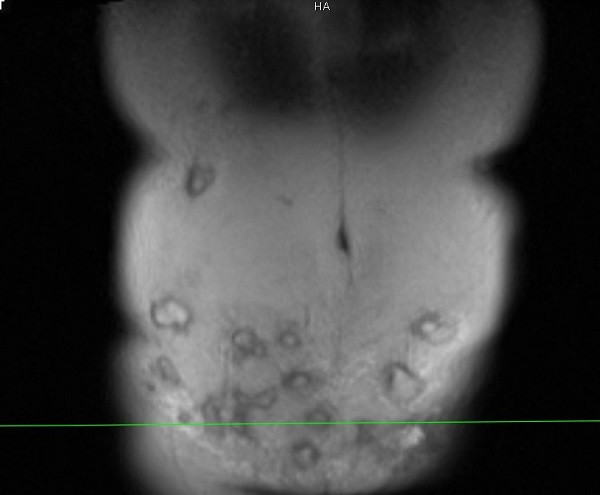

Spa này tiêm rất nhiều mũi vào thành bụng dưới của bệnh nhân, đồng thời tiêm cả trên vùng hạ sườn hai bên. Sau tiêm khoảng 1 tháng, chị T. đau vùng bụng dưới và tới Bệnh viện E để thăm khám, tạo hình lại thành bụng.

Bác sĩ Minh cho biết, vùng thành bụng bệnh nhân bị viêm phản ứng nặng, vùng da ngoài thành bụng đỏ, nổi gồ ghề, sờ bên dưới có hàng chục khối tổ chức vón cục, áp xe....

“Bệnh nhân này có thể tạo hình lại thành bụng, đồng thời giải quyết được 20 khối áp xe lớn nhỏ. Tuy nhiên, do vùng tiêm rộng nên việc lấy hết ổ áp xe này không dễ dàng. Với những khối áp xe tiêm ở vị trí cao như hạ sườn thì quá trình xử lý sẽ để lại sẹo, gây mất thẩm mỹ”, bác sĩ Minh chia sẻ.